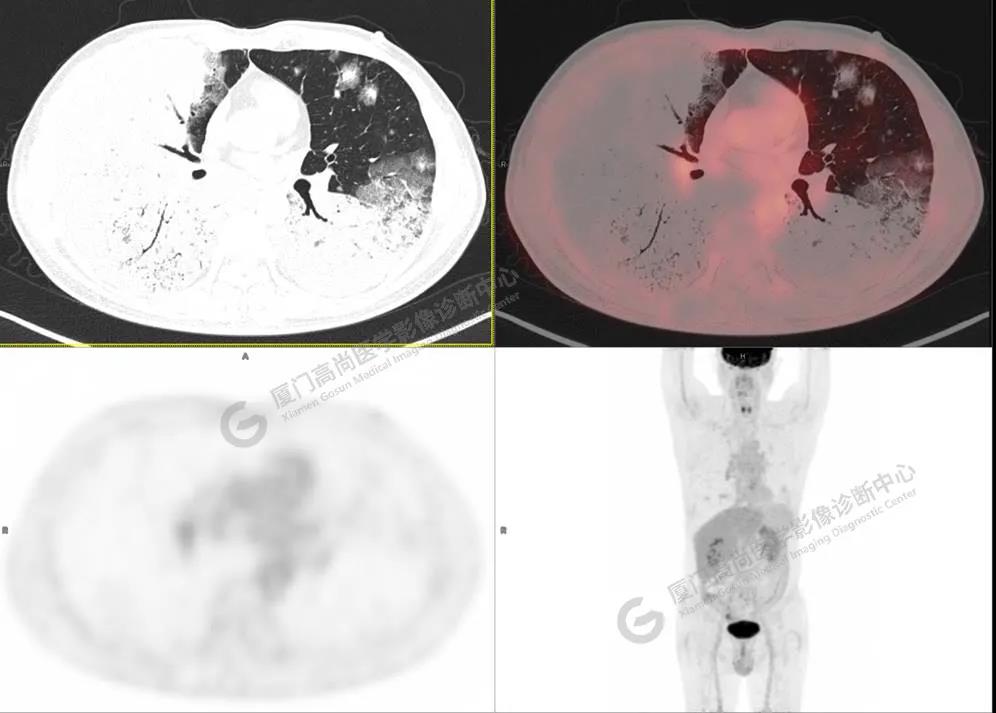

圖3

PET/CT所見:雙肺大片實(shí)變影及磨玻璃影,部分呈地圖樣改變,累及右肺尖,部分放射性攝取輕微增高,SUVmax 1.77,其內(nèi)見多發(fā)支氣管充氣征象。

影像診斷: 雙肺大片實(shí)變影及磨玻璃影,大部分代謝不高,局部代謝輕微增高,考慮肺泡蛋白沉積癥,建議病理學(xué)檢查或肺泡灌洗物檢查。

影像學(xué)表現(xiàn):HRCT上雙肺斑片影,以肺門為中心呈蝶翼狀對稱分布;病變可隨機(jī)分布在中央?yún)^(qū)、周圍區(qū)或全肺葉,病灶與正常分組織分界清楚,呈典型“地圖樣”改變;有支氣管充氣征,但表現(xiàn)為充氣支氣管細(xì)小且數(shù)量及分布稀少;“碎石路”征由彌漫性磨玻璃影及內(nèi)部網(wǎng)格樣小葉間隔增厚組成(鋪路石樣表現(xiàn))。無空洞、蜂窩狀改變、淋巴結(jié)腫大、胸腔積液及明顯實(shí)變等。肺內(nèi)病灶累及范圍、磨玻璃密度高低與PAP患者的病情嚴(yán)重程度相關(guān),嚴(yán)重者病灶累及全肺,同時出現(xiàn)肺內(nèi)大片實(shí)變,并見充氣支氣管征象。PAP影像學(xué)表現(xiàn)程度與臨床癥狀、體征嚴(yán)重程度不成比例,表現(xiàn)為影像改變重,臨床癥狀輕。